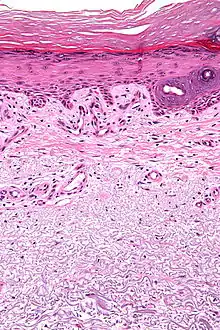

| Micrograph showing solar elastosis - grey, jumbled spaghetti-like material on bottom of image. H&E stain. | |

In the earlier stages of actinic elastosis, elastic fiber proliferation can be seen in the dermis. As the condition becomes more established, the collagen fibers of the papillary dermis and reticular dermis become increasingly replaced by thickened and curled fibers that form tangled masses and appear basophilic under routine haematoxylin and eosin staining. These fibers stain black with the Verhoeff stain.[2]